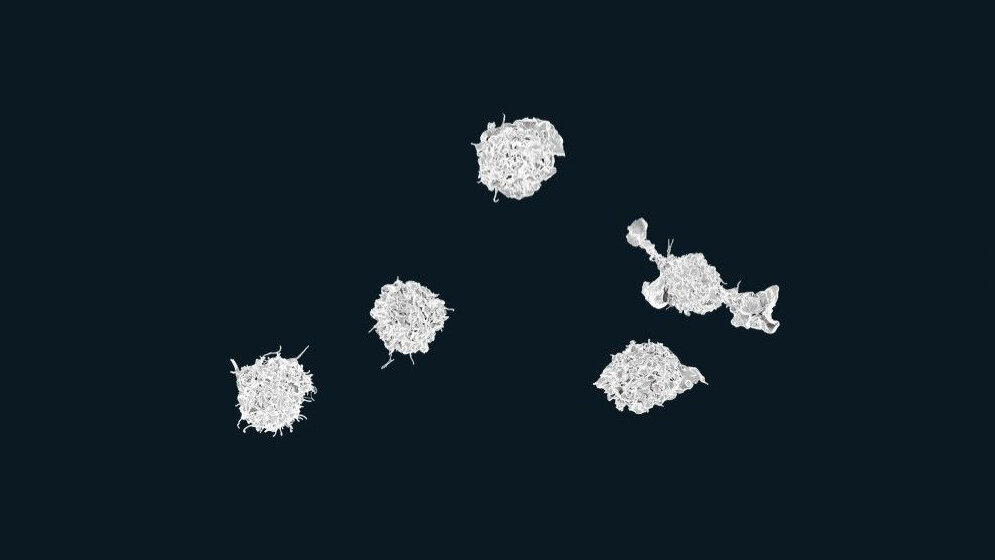

Der Bluttest basiert auf der EDIM-Technologie. Sie beruht darauf, dass Makrophagen durch den Körper „patrouillieren“ und dabei ungewünschte Zellstrukturen, wie beispielsweise Bakterien, Viren oder eben auch entartete körpereigene Zellen, aufnehmen. Bei der EDIM-Technologie ist es das Ziel, diese „gefressenen“ Zellstrukturen – im Falle des PanTum Detect durch die Biomarker TKTL1 und Apo10, die charakteristisch sind für solide Tumore – im Innern der Makrophagen nachgewiesen werden. Dafür bedarf es lediglich einer einfachen Blutprobe.

Mit der Detektionstechnologie von EDIM soll so das körpereigene Immunsystem zum Indikator für Tumorentwicklungen werden. Das Immunsystem ist evolutionär dazu ausgebildet, im Körper entartete Zellen und körperfremde Zellen aufzuspüren und zu phagozytieren. Diese Vorgänge erfolgen hochspezifisch, da Makrophagen die Zellen nur dann fressen, wenn diese sie als entartet erkennen. Deshalb ist laut Zyagnum die Problematik falsch positiver (und auch falsch negativer) Ergebnisse dabei äußerst gering: Der PanTum Detect soll Tumore mit einer Sensitivität von 97,5 Prozent bei einer Spezifität von 99,53 Prozent nachweisen. Das heißt, 97,5 Prozent aller Tumore sollen mit dem Test detektiert werden, und nur einer von 200 gesunden Patienten würde dann als falsch positiv erkannt.